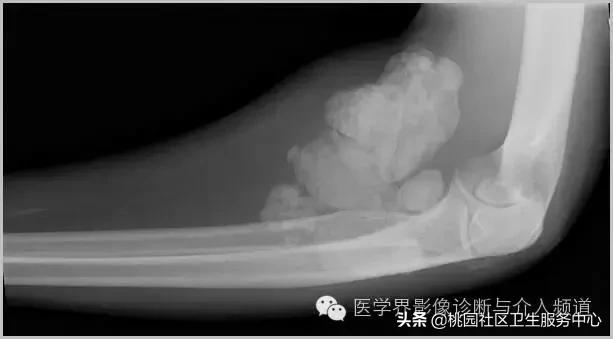

一、肿瘤样钙质沉着症

累及多个关节,范围较大,表现为多房囊状的高密度影。

肿瘤样钙质沉着症